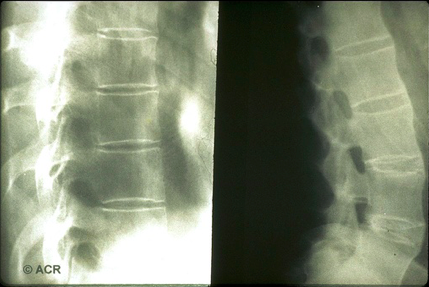

What is a syndesmophyte?

What do you see here?

What are the x-ray findings with AS?